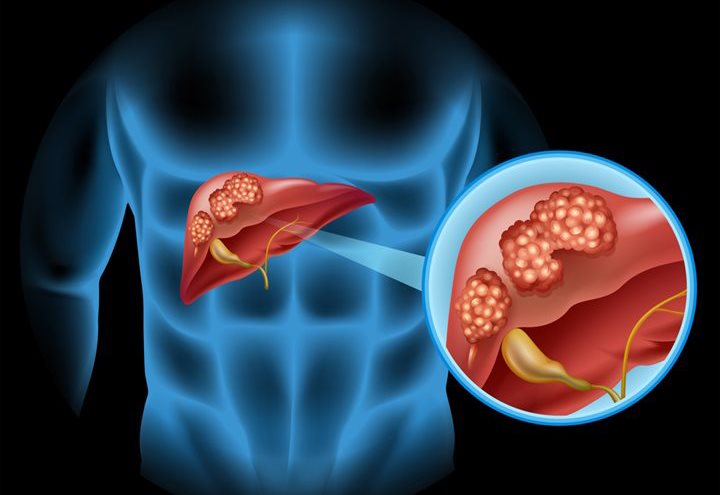

When health care professionals make any diagnosis of cancer it is taken seriously due to the severe and possibly life-threatening complications that may come with the disease. Patients are not typically screened for liver cancer, although those with high risks of developing it may be screened. High-risk patients include people with...